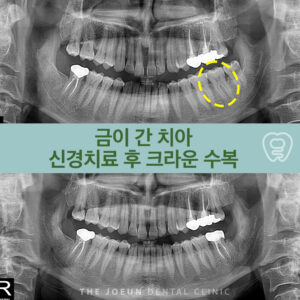

잇몸뼈가 가장 약했던 오른쪽 위 어금니 부위는 다른 부위에 모든 보철물을 합착한 뒤 식립을 진행하였는데요.